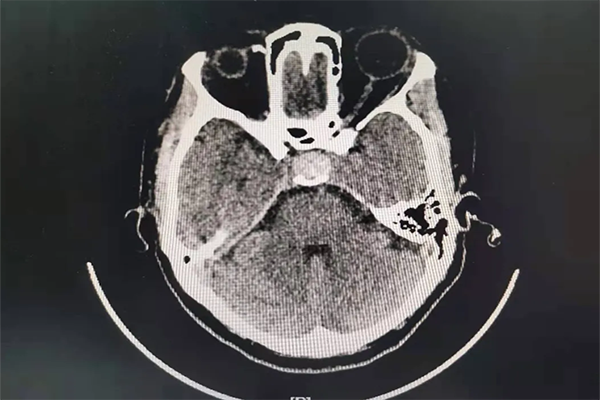

患者段女士,42歲。反復頭暈、眼花、心慌已經5月多了,5月前當地醫院頭顱CT未見明顯異常。1周前患者頭暈、眼花越發嚴重,輾轉多個醫院無果后,患者來到我院內科住院檢查,完善頭顱CT后,發現鞍區占位,考慮垂體腺瘤可能。

當外一科楊金雷主任到達內科時,已經找不到段女士的身影了。楊主任通過查看患者病歷,電腦閱讀CT,診斷患者為垂體腺瘤并出血可能,即患者可能存在瘤卒中。要求立刻打電話讓患者返回醫院接受正規系統的治療。

5個月的時間,CT結果提示鞍區占位病變,進行性增大,考慮瘤卒中可能。